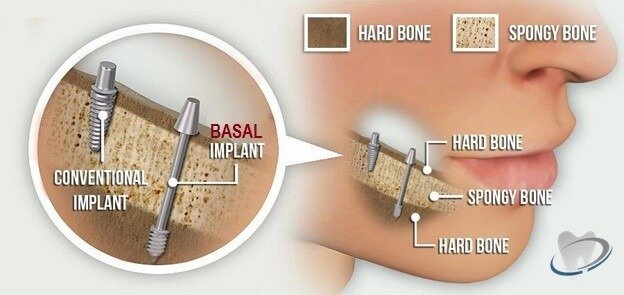

At our clinic, we offer two primary types of implants depending on your bone health and clinical needs: Conventional Dental Implants and Basal Dental Implants.

Conventional implants are the most commonly used type of implant worldwide. These implants require sufficient bone volume and density for placement. In cases of bone loss, patients may need bone grafting procedures before receiving conventional implants.

Basal implants, also known as cortical or basal osseointegrated implants, are a revolutionary solution for patients with significant bone loss. Unlike conventional implants that rely on spongy bone (alveolar bone), basal implants are anchored in the basal bone, which is the strong, stable part of the jaw that remains even in cases of severe bone resorption.